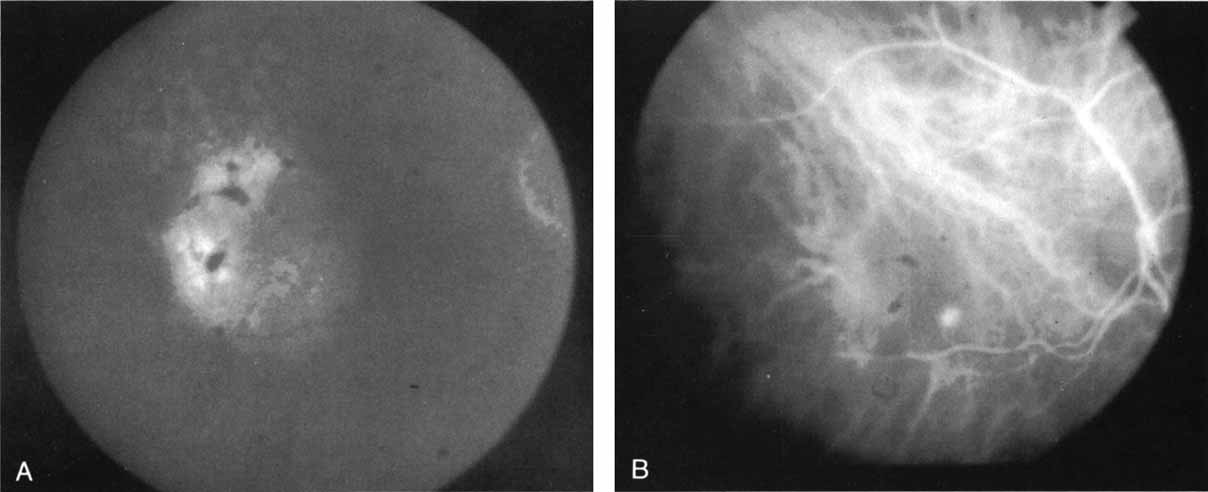

MULTIFOCAL CHOROIDITIS

Most promising in this category of inflammatory choroidopathies is a better detection and understanding of the lesions of multifocal choroiditis. Multiple large, scattered, hypofluorescent spots are seen on ICG angiography, particularly in the later phases of the angiogram69 (Fig. 18). These lesions are not evident either on clinical examination or on fluorescein angiography. In addition to having these larger hypofluorescent lesions, patients with multifocal choroiditis have smaller dot-like lesions and hyperfluorescent foci that do not correlate with lesions seen clinically or by FA. They involve the posterior pole and in some patients extend into the mid-periphery. There is also a “papillotropic” involvement, with confluent hypofluorescent lesions surrounding the optic nerve,69 which may be useful in understanding the associated blind-spot enlargement evident in this condition.70 Other zonal visual field defects have been associated with this condition,70 and corresponding ICG abnormalities have been documented in some patients.69

Fig. 18 A. Clinical photograph of a patient with active inflammation associated with multifocal choroiditis. An atrophic scar from previous laser photocoagulation treatment is noted in the temporal macula. The patient reported visual disturbance, and an enlarged blind spot was noted on visual field testing. B. Late-phase indocyanine green study demonstrating a multitude of hypofluorescent spots that were larger than those seen with multiple evanescent white dot syndrome and more numerous and more extensively distributed than appreciated on clinical examination. Note that there is marked confluence of these lesions around the optic nerve, which may help to explain the enlarged blind spot noted on visual field testing.

Natural history data indicate that with progressive increase in vitritis and associated choroidal inflammation, an increase in the number and extent of these hypofluorescent lesions can be documented.40 Furthermore, use of oral steroid therapy as a means of controlling this inflammatory process has been documented to produce not only clinical resolution of the inflammatory process but also corresponding resolution of the hypofluorescent lesions seen on ICG angiography.69 These clearly demonstrated lesions not only may lead to a better understanding of the process of inflammation involved in multifocal choroiditis and potential management strategies but also may serve to differentiate this condition from the ocular histoplasmosis syndrome.